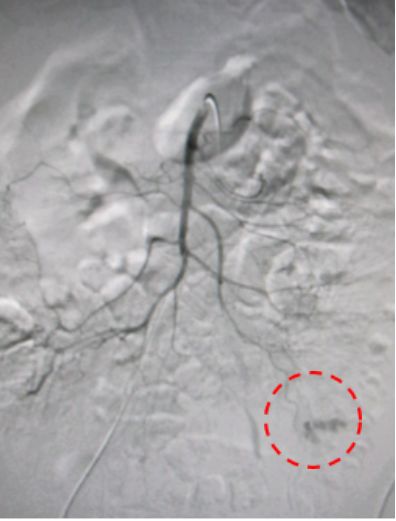

左肾取石术后血尿,造影发现左肾动脉分支出血。

治疗前

介入栓塞后出血停止,血尿消失。

治疗后